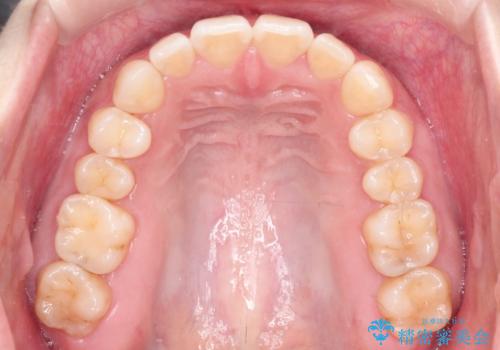

【インビザライン】前歯が出てるのを治したい

- 前歯の凸凹と前突を主訴に来院されました。

インビザラインにて治療をおこない、歯並びを改善することができました。